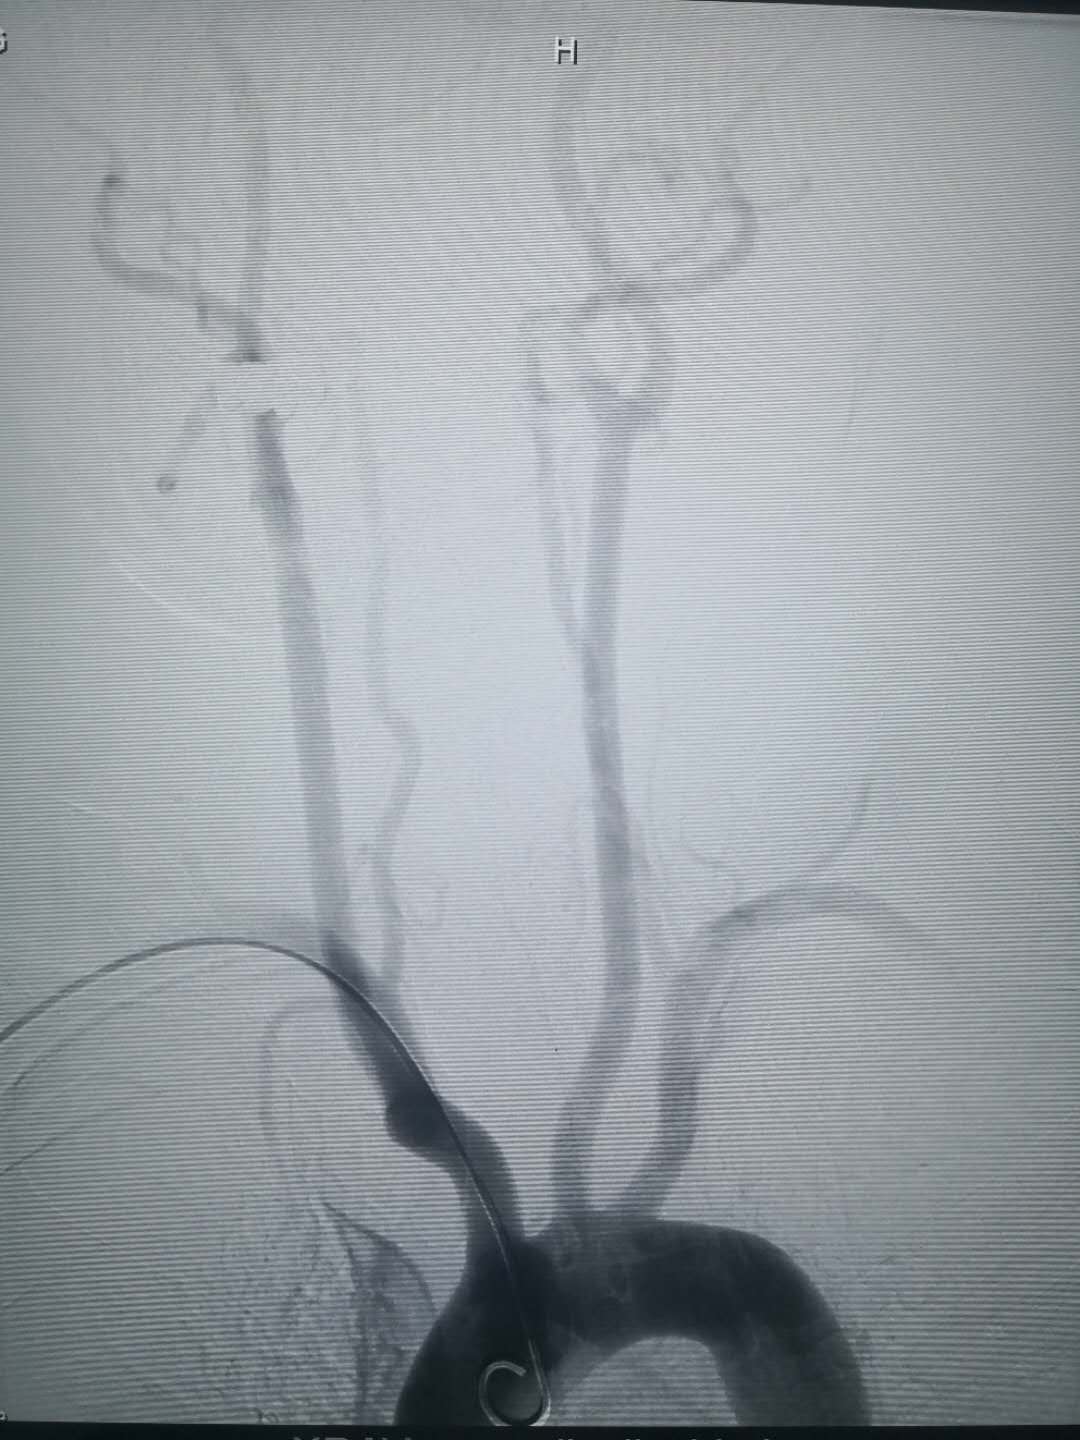

置入造影導管后相關血管造影圖,所選擇的血管清晰可見

經動脈鞘管置入造影導管行造影術 經橈動脈穿刺置入動脈鞘管 術后:使用小巧的橈動脈壓迫器壓迫固定橈動脈